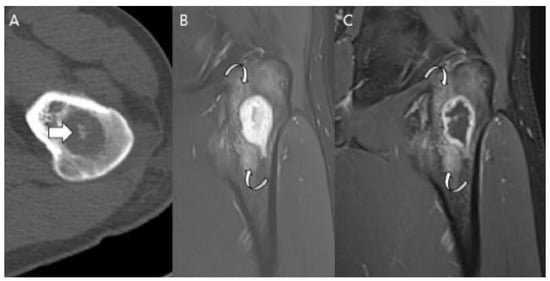

3.3. Distinction between ACT/CS1 and High-Grade Chondrosarcoma

4. Current Treatments and Management